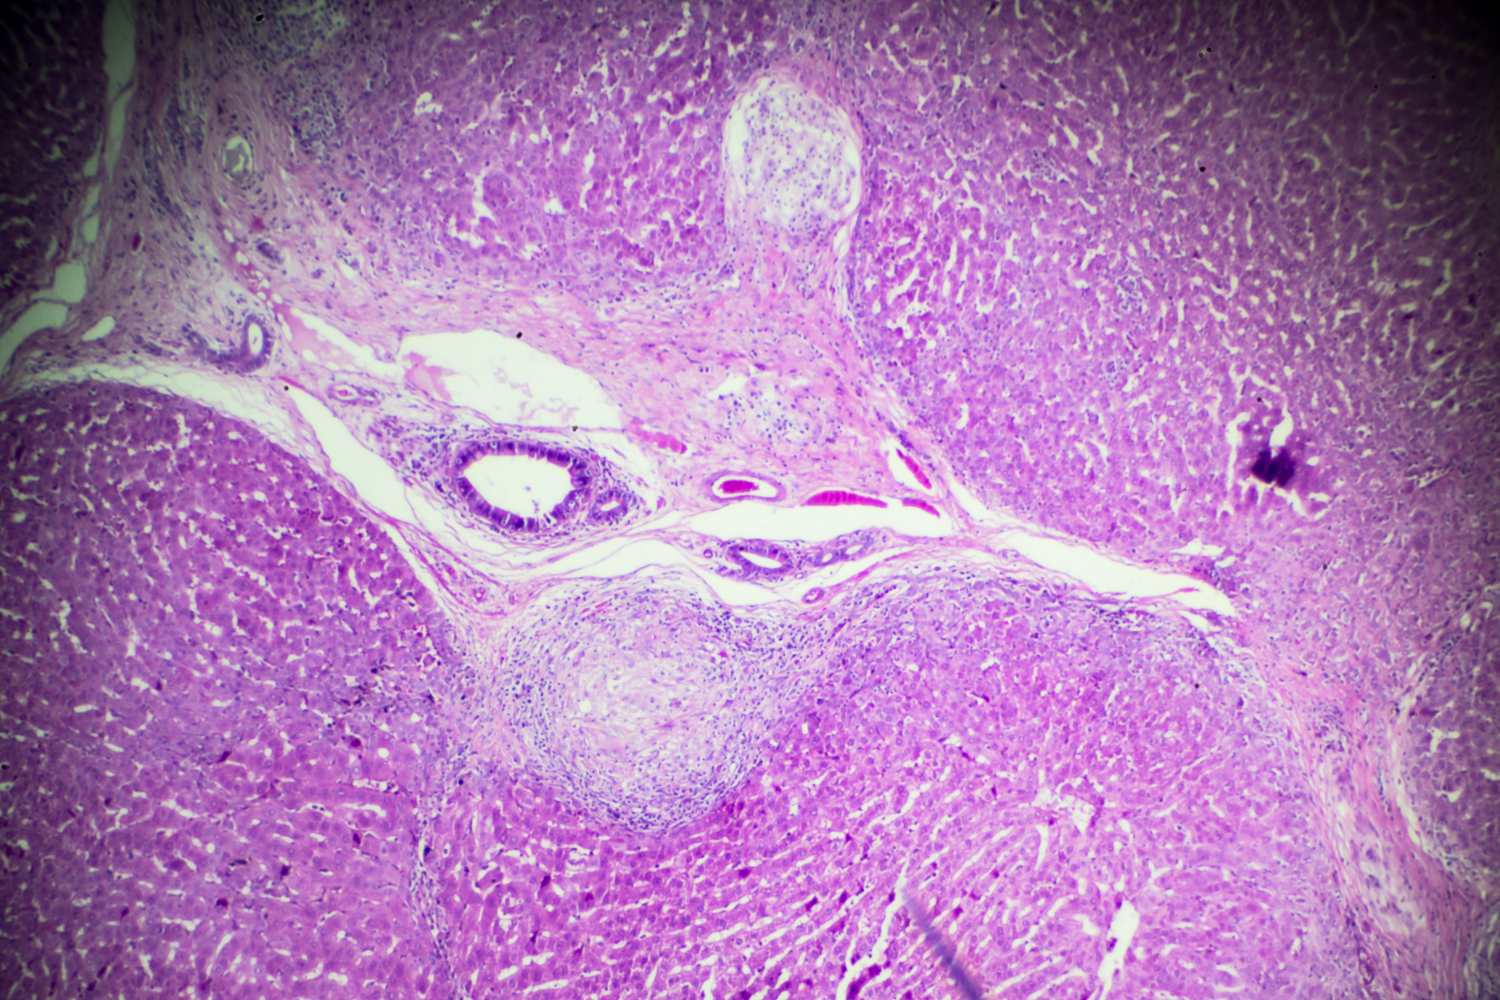

esquistosomiasis 2

El ciclo de vida del parásito es complejo. Los huevos son expulsados ​​con las heces humanas y, si llegan a agua dulce, eclosionan liberando las larvas que infectan a especies específicas de caracoles de agua. En el interior de estos moluscos, los parásitos se multiplican y se transforman en cercarias, formas larvarias dotadas de una cola bifurcada que les permite nadar.

Como se mencionó, las investigaciones han demostrado cómo el parásito es capaz de secretar moléculas capaces de bloquear los receptores del dolor y la picazón, una estrategia evolutiva que permite al gusano completar la invasión antes de que el sistema inmunológico pueda organizar una respuesta efectiva. Una vez dentro, el parásito pierde la cola y migra por los vasos sanguíneos hasta llegar a los pulmones, luego al hígado y finalmente a las venas intestinales, donde madura y se reproduce.

En las primeras horas después de la infección, algunas personas desarrollan una dermatitis llamada “picazón del nadador”, con pequeñas manchas rojas en la piel. Después de cuatro a seis semanas, cuando los gusanos comienzan a poner huevos, aparecen síntomas más graves: fiebre, dolores musculares, tos y diarrea con sangre. Los huevos que quedan atrapados en los tejidos provocan inflamación crónica.

Con el paso de los años, la esquistosomiasis puede provocar daños permanentes en el hígado, los intestinos, la vejiga y otros órganos, mientras que en los niños la infección crónica perjudica el crecimiento y el desarrollo cognitivo. La enfermedad puede tratarse con praziquantel, un fármaco antiparasitario barato y eficaz, aunque los casos de reinfección son muy frecuentes en zonas endémicas.